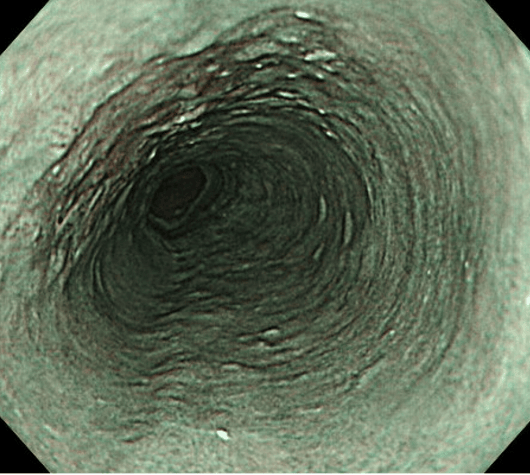

食物がのどを通りにくい、嘔吐するなどの症状がある場合、食道アカラシアを疑い検査を行います。食道アカラシアとは下部食道活躍部の弛緩不全と食道全体の蠕動運動障害を認める原因不明の食道運動機能障害です。食道造影検査(バリウムによる透視検査)、上部消化管内視鏡、食道内圧検査(食道内の圧力測定)で診断します。薬物療法やバルーン拡張などの治療では症状の劇的な改善は少ないとされ、奏功しない場合には経口内視鏡治療(POEM)や手術療法(Heller-Dor手術)を行います。POEMは安全性と低侵襲が認められた標準内視鏡治療です。食道筋層をイラストのように切開していくことで食道運動機能改善へと繋がります。低侵襲でありながら治療効果は手術と同等であるとされています。そのため、食事摂取も可能となり日常生活においてQOLの向上に繋がります。